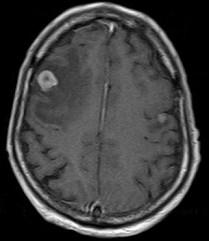

问题 大脑半球肿瘤(如图所示)的临床表现有()

选项 A.精神症状 B.癫痫发作 C.感觉障碍 D.运动障碍 E.视野缺损

答案 ABCDE